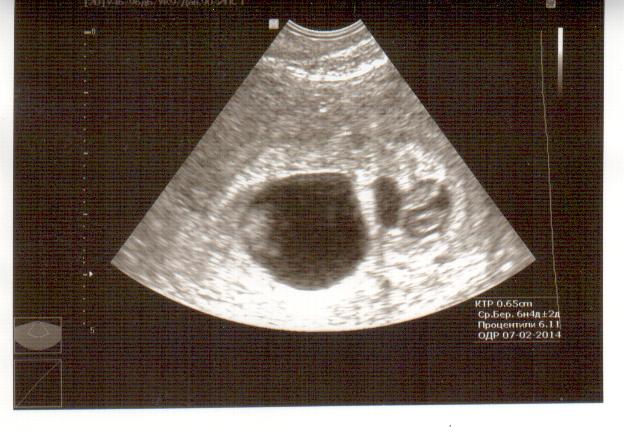

Узи 7 недель. Двойня? Тройня?

УЗИ, КТГ, доплер, скрининг, ХГЧ и другие анализыДевочки,у кого есть опыт... У меня узи странное. Живу в маленьком городе -специалисты на среднем уровне,сегодня видела сердцебиение 2-х деточек! Я после эко,посадили 2 эмбриончика. Но на узи говорят,что похоже трех подсаживали.Не могу фотку разместить :( ,она в альбоме у меня.Посмотрите,пожалуйста!

Вполне возможно, что подсаживали двух, но одно яйцо разделилось, поэтому и разные по диаметру. Подождите пару недель и повторите УЗИ. Я поздравляю вас с беременностью и прекрасно понимаю ваше сметение)))